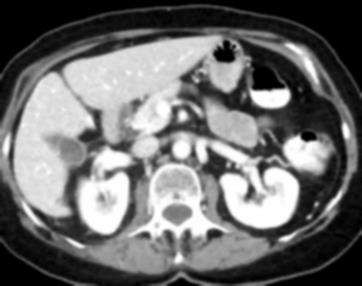

Due to the constraints of the imaging device and high cost in operation time, computer tomography (CT) scans are usually acquired with low intra-slice resolution. Improving the intra-slice resolution is beneficial to the disease diagnosis for both human experts and computer-aided systems. To this end, this paper builds a novel medical slice synthesis to increase the between-slice resolution. Considering that the ground-truth intermediate medical slices are always absent in clinical practice, we introduce the incremental cross-view mutual distillation strategy to accomplish this task in the self-supervised learning manner. Specifically, we model this problem from three different views: slice-wise interpolation from axial view and pixel-wise interpolation from coronal and sagittal views. Under this circumstance, the models learned from different views can distill valuable knowledge to guide the learning processes of each other. We can repeat this process to make the models synthesize intermediate slice data with increasing inter-slice resolution. To demonstrate the effectiveness of the proposed approach, we conduct comprehensive experiments on a large-scale CT dataset. Quantitative and qualitative comparison results show that our method outperforms state-of-the-art algorithms by clear margins.